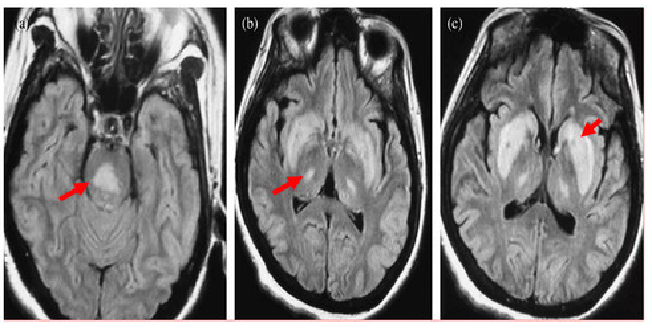

影像学特征

CT表现为脑桥中央或脑桥外病灶处的低密度影。

MRI能更好地反映病灶的数量和程度。早期可无异常,出现症状后1周DWI上可发现高信号。急性期表现为对称的T1WI低信号,亚急性期可能是由于内皮细胞受损所致的微出血而显示T2WI高信号。FLAIR显示病灶高信号更清楚,能更好地显示临近脑脊液的病灶,比如大脑皮质,应作为常规检查。也有一些报道发现皮质层及皮质下T1高信号,有的钆增强被强化,有的不被强化。脑MRI对本病具有十分重要的诊断意义,大约在发病2~3周时异常信号最为明显,所以结合病史及临床表现如果考虑ODS的诊断,在MRI检查正常的情况下,在出现症状后10~14天复查MRI是十分重要和必要的。